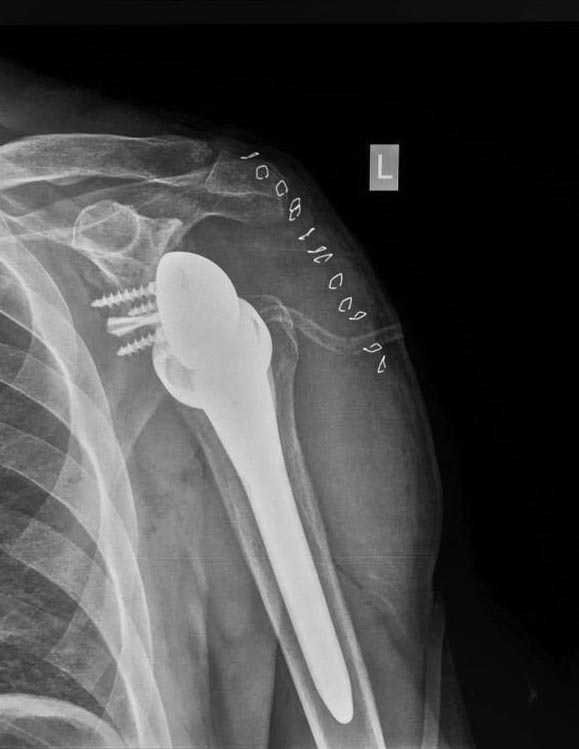

[Ortho] Перелом проксимального метаэпифиза плеча